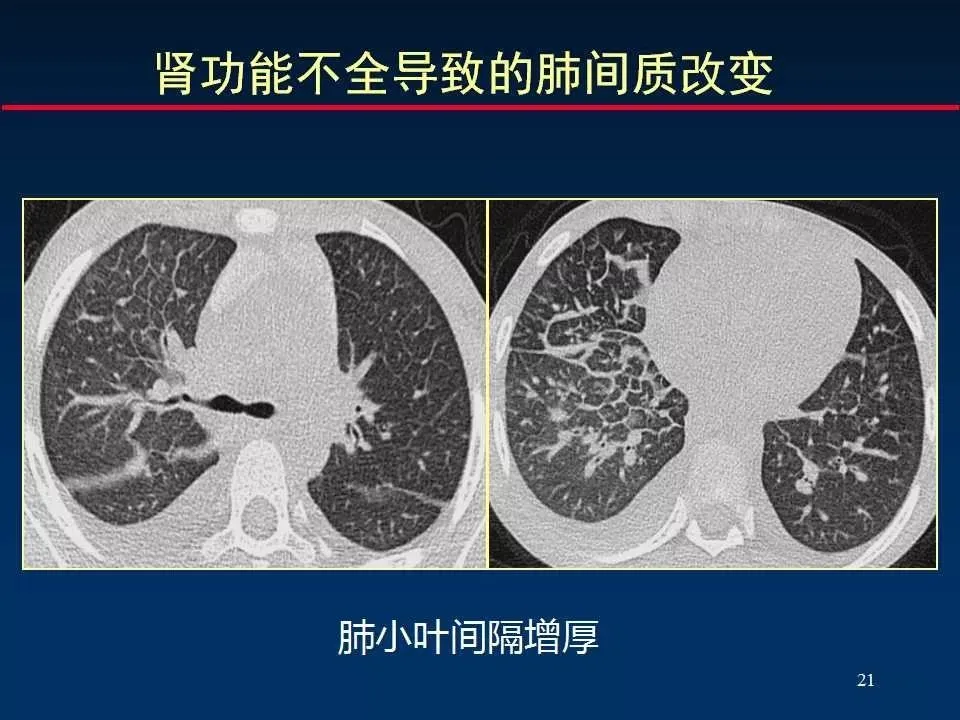

3、网格状改变 reticular opacity (小叶间隔增厚)